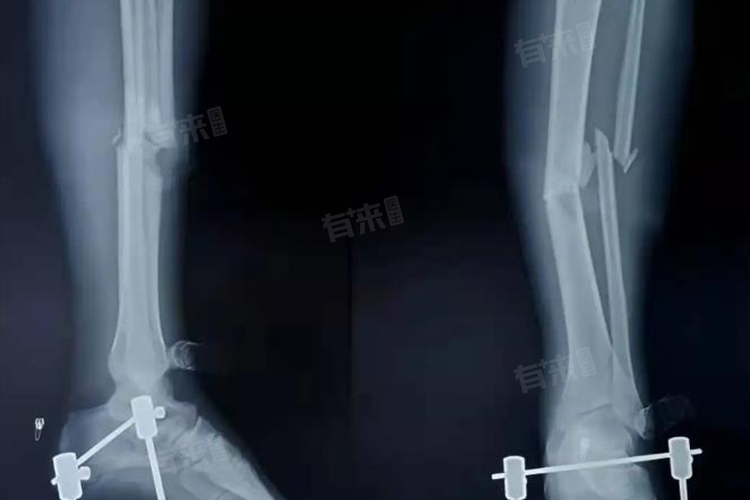

2、固定不良:骨折后的固定对于愈合非常重要,如果固定不牢固,骨折部位可能会反复移动,影响骨痂形成。外固定器具不合适或孩子活动过度容易导致固定松动,需定期检查固定情况,确保其稳定性。